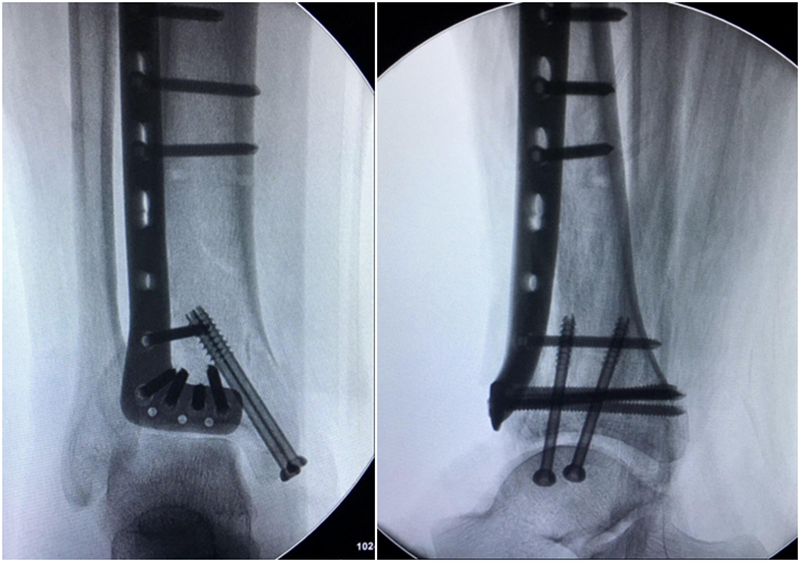

术后影像学资料: